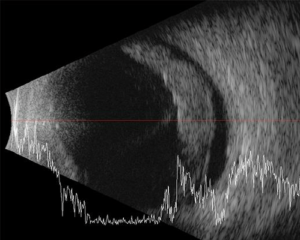

انفصال الشبكية

انفصال الشبكية هي حالة طبية خطيرة تحدث عند انفصال الطبقة الحساسة في الجزء الخلفي من العين، المعروفة بالشبكية، عن الجزء الداعم لها المعروف باسم الجسم الزجاجي، ويتمثل دور الشبكية في استقبال الضوء وتحويله إلى إشارات عصبية تُرسل إلى الدماغ عبر العصب البصري لتكوين الصورة.

عندما يحدث انفصال الشبكية، يمكن أن يشعر الشخص بومض في الرؤية أو رؤية وميض ضوء، يليه فقدان مفاجئ للرؤية في منطقة معينة .

تظهر أعراض انفصال الشبكية عادةً بشكل فجائي مثل الرؤية المتوهجة، وظهور ومضات ضوء، وفقدان جزئي أو كامل للرؤية، ويتطلب علاج انفصال الشبكية إجراء جراحي لإعادة وصلها بالجزء الداخلي للعين، ومن المهم أن يتم التشخيص والعلاج الفوري لتجنب تدهور الحالة وتقليل فقدان الرؤية بشكل دائم.